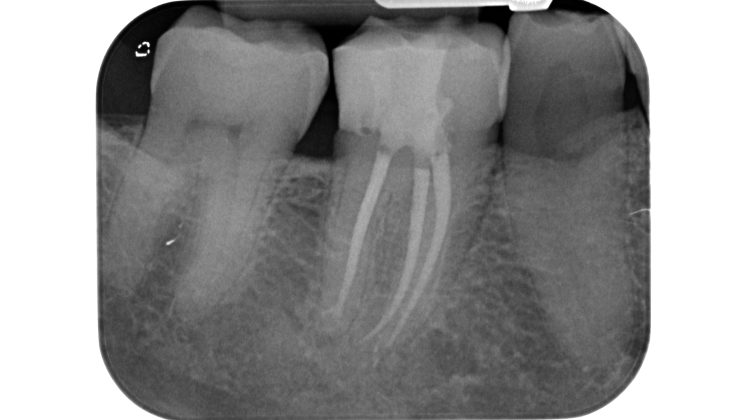

Nei molari la distanza tra la sommità di qualsiasi cuspide e il tetto della camera pulpare è di circa 6,3 mm, nei premolari superiori è di 6,94 mm.

La camera pulpare ha un’altezza di circa 1,5-2 mm e la distanza media dal pavimento della camera alla forca è di 3 mm circa (Tabella 1) (Figura 13).

La fresa che ci guida in questo step ha una parte lavorante di 6 mm (Komet 880-314-012) che, ricordando una delle regole di Deutsch, non dovrà penetrare oltre il nostro punto di repere occlusale: diventerebbe alto il rischio di sovra estendere la preparazione e di indebolire se non di perforare il pavimento (Figura 14).